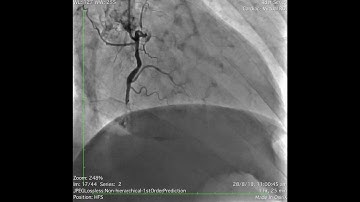

Complex PCI for RCA CTO with bifurcation at distal cap video 1